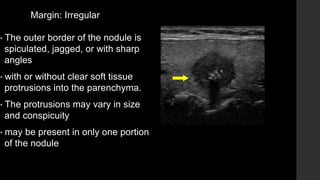

Margin: Irregular

• The outer border of the nodule is

spiculated, jagged, or with sharp

angles

• with or without clear soft tissue

protrusions into the parenchyma.

• The protrusions may vary in size

and conspicuity

• may be present in only one portion

of the nodule